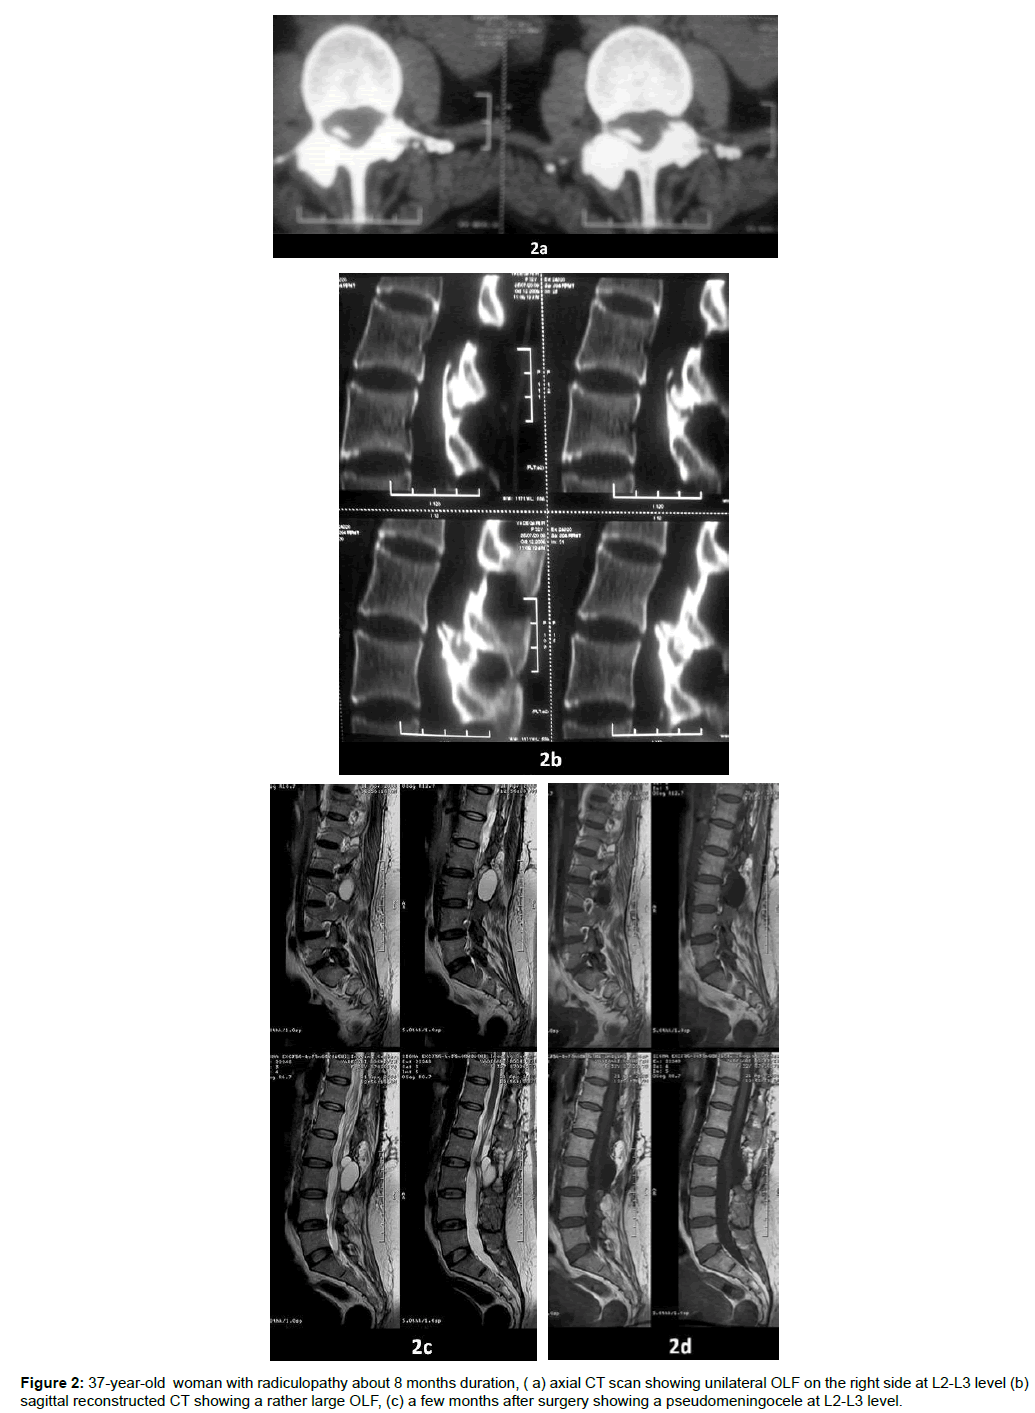

All patients showed good recovery except one who was readmitted because of low back pain in straining and coughing. In this case, further evaluation showed pseudomeningocele formation which was cured after a redo surgery.

| 2 | F | 37 | Radiculopathy | L2-L3 | Laminectomy | Good |